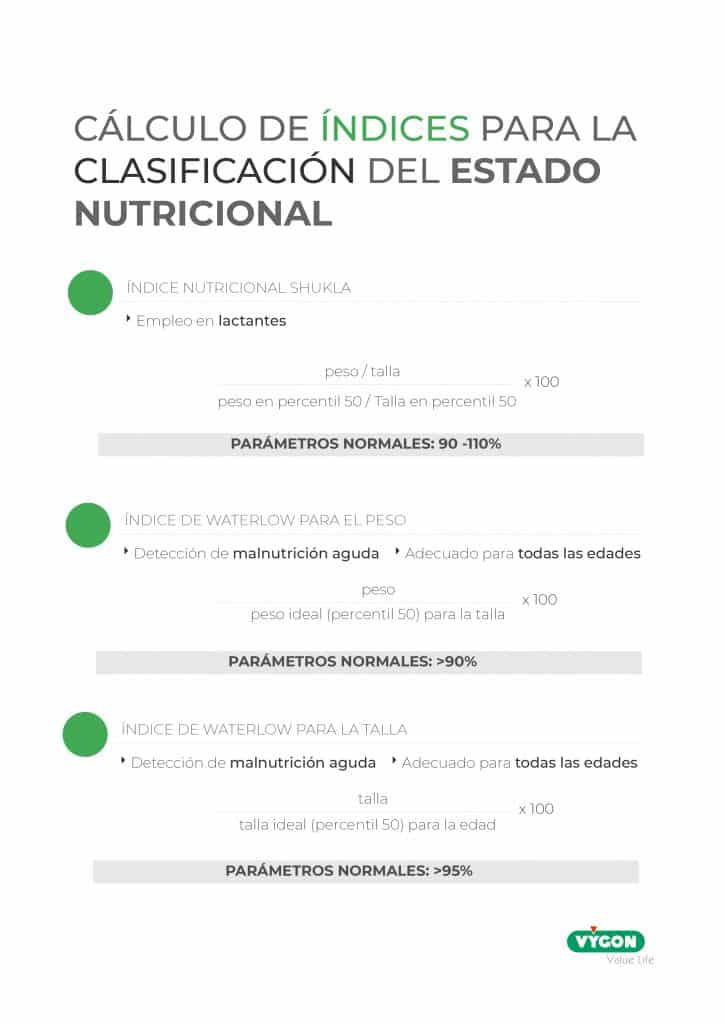

- Valoración clínica de la talla y composición corporal del neonato. Este procedimiento evaluará el peso, talla, perímetro braquial, pliegue tricipital y graso del paciente. Estos datos permitirán el cálculo de índices que ayudarán en la clasificación del estado nutricional del paciente (puedes utilizar la siguiente infografía para ello). La valoración puede completarse con el análisis de otras variables como: patrones de crecimiento, estimación del gasto energético, parámetros bioquímicos…